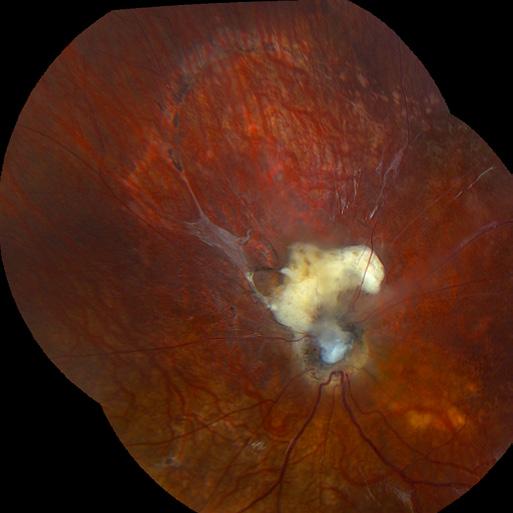

Sunny, an 8-year-old Mouse Lemur presented for blindness OU. The patient was evaluated initially in the cage for visual responses and ability to navigate the enclosure. The was an absent menace and tracking but present dazzle response and PLR OU. The mouse lemur was sedated for ophthalmic examination via slit lamp biomicroscopy and indirect ophthalmoscopy. On presentation, there was a mid-immature cataract OD and a late immature cataract OS. Anisocoria with a focal area of posterior synechia causing dyscoria OS. On fundic examination there was advanced retinal degeneration as appreciated by diffuse hyperreflectivity (due to increased tapetal reflection) and severe vascular attenuation (normal is a radial holangiotic retinal vasculature pattern). The optic nerve was moderately degenerated. Tonometry performed by TonoPen (applanation tonometer): 10 mmHg OD, 4 mmHg OS.

The Journal of Ophthalmic Photography Volume 45, Issue 1 • 2023 12

Additional Exams Performed by Dr. LaFoon Marshall, a 1.5 yo mixed breed canine, is shown with a corneal dermoid of the right eye adjacent to the limbus. Note the haired pigmented keratinized epithelium causing the mass effect approximately 8 mm in diameter adjacent to the limbus OD. Keratectomy was recommended for removal, which was performed uneventfully under general anesthesia.

13 An Afternoon

with

Dr. Brooklyn Lafoon

6-year-old Schnauzer presented for diabetic cataracts OU. Images are post bilateral phacoemulsification with artificial lens implantation.

Cat presented for lens capsule rupture with mature cataract and proliferative like tissue extruding through the pupil with significant preiridal fibrovascular membrane. Enucleation showed intralenticular hyphae.